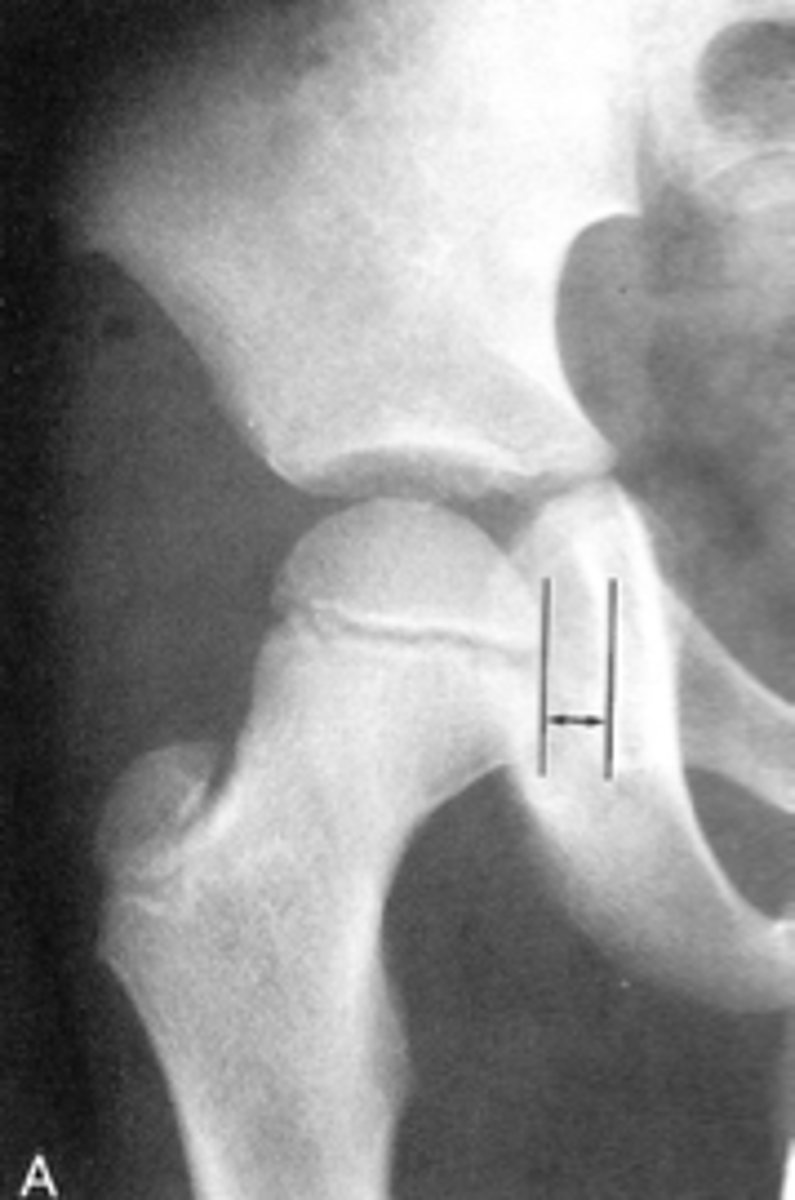

Femoral angle

ID measurement

<p>ID measurement</p>

- AP pelvis

- AP hip

What views are used to measure the femoral angle?

<p>What views are used to measure the femoral angle?</p>

- Mid-axis of femoral shaft

- Mid-axis of femoral neck

- Intervening angle

Femoral angle landmarks

<p>Femoral angle landmarks</p>

120-130˚

Normal femoral angle measurement

<p>Normal femoral angle measurement</p>

Coxa vara

Femoral angle <120˚

<p>Femoral angle &lt;120˚</p>

68

Coxa valga

Femoral angle >130˚

<p>Femoral angle &gt;130˚</p>

69